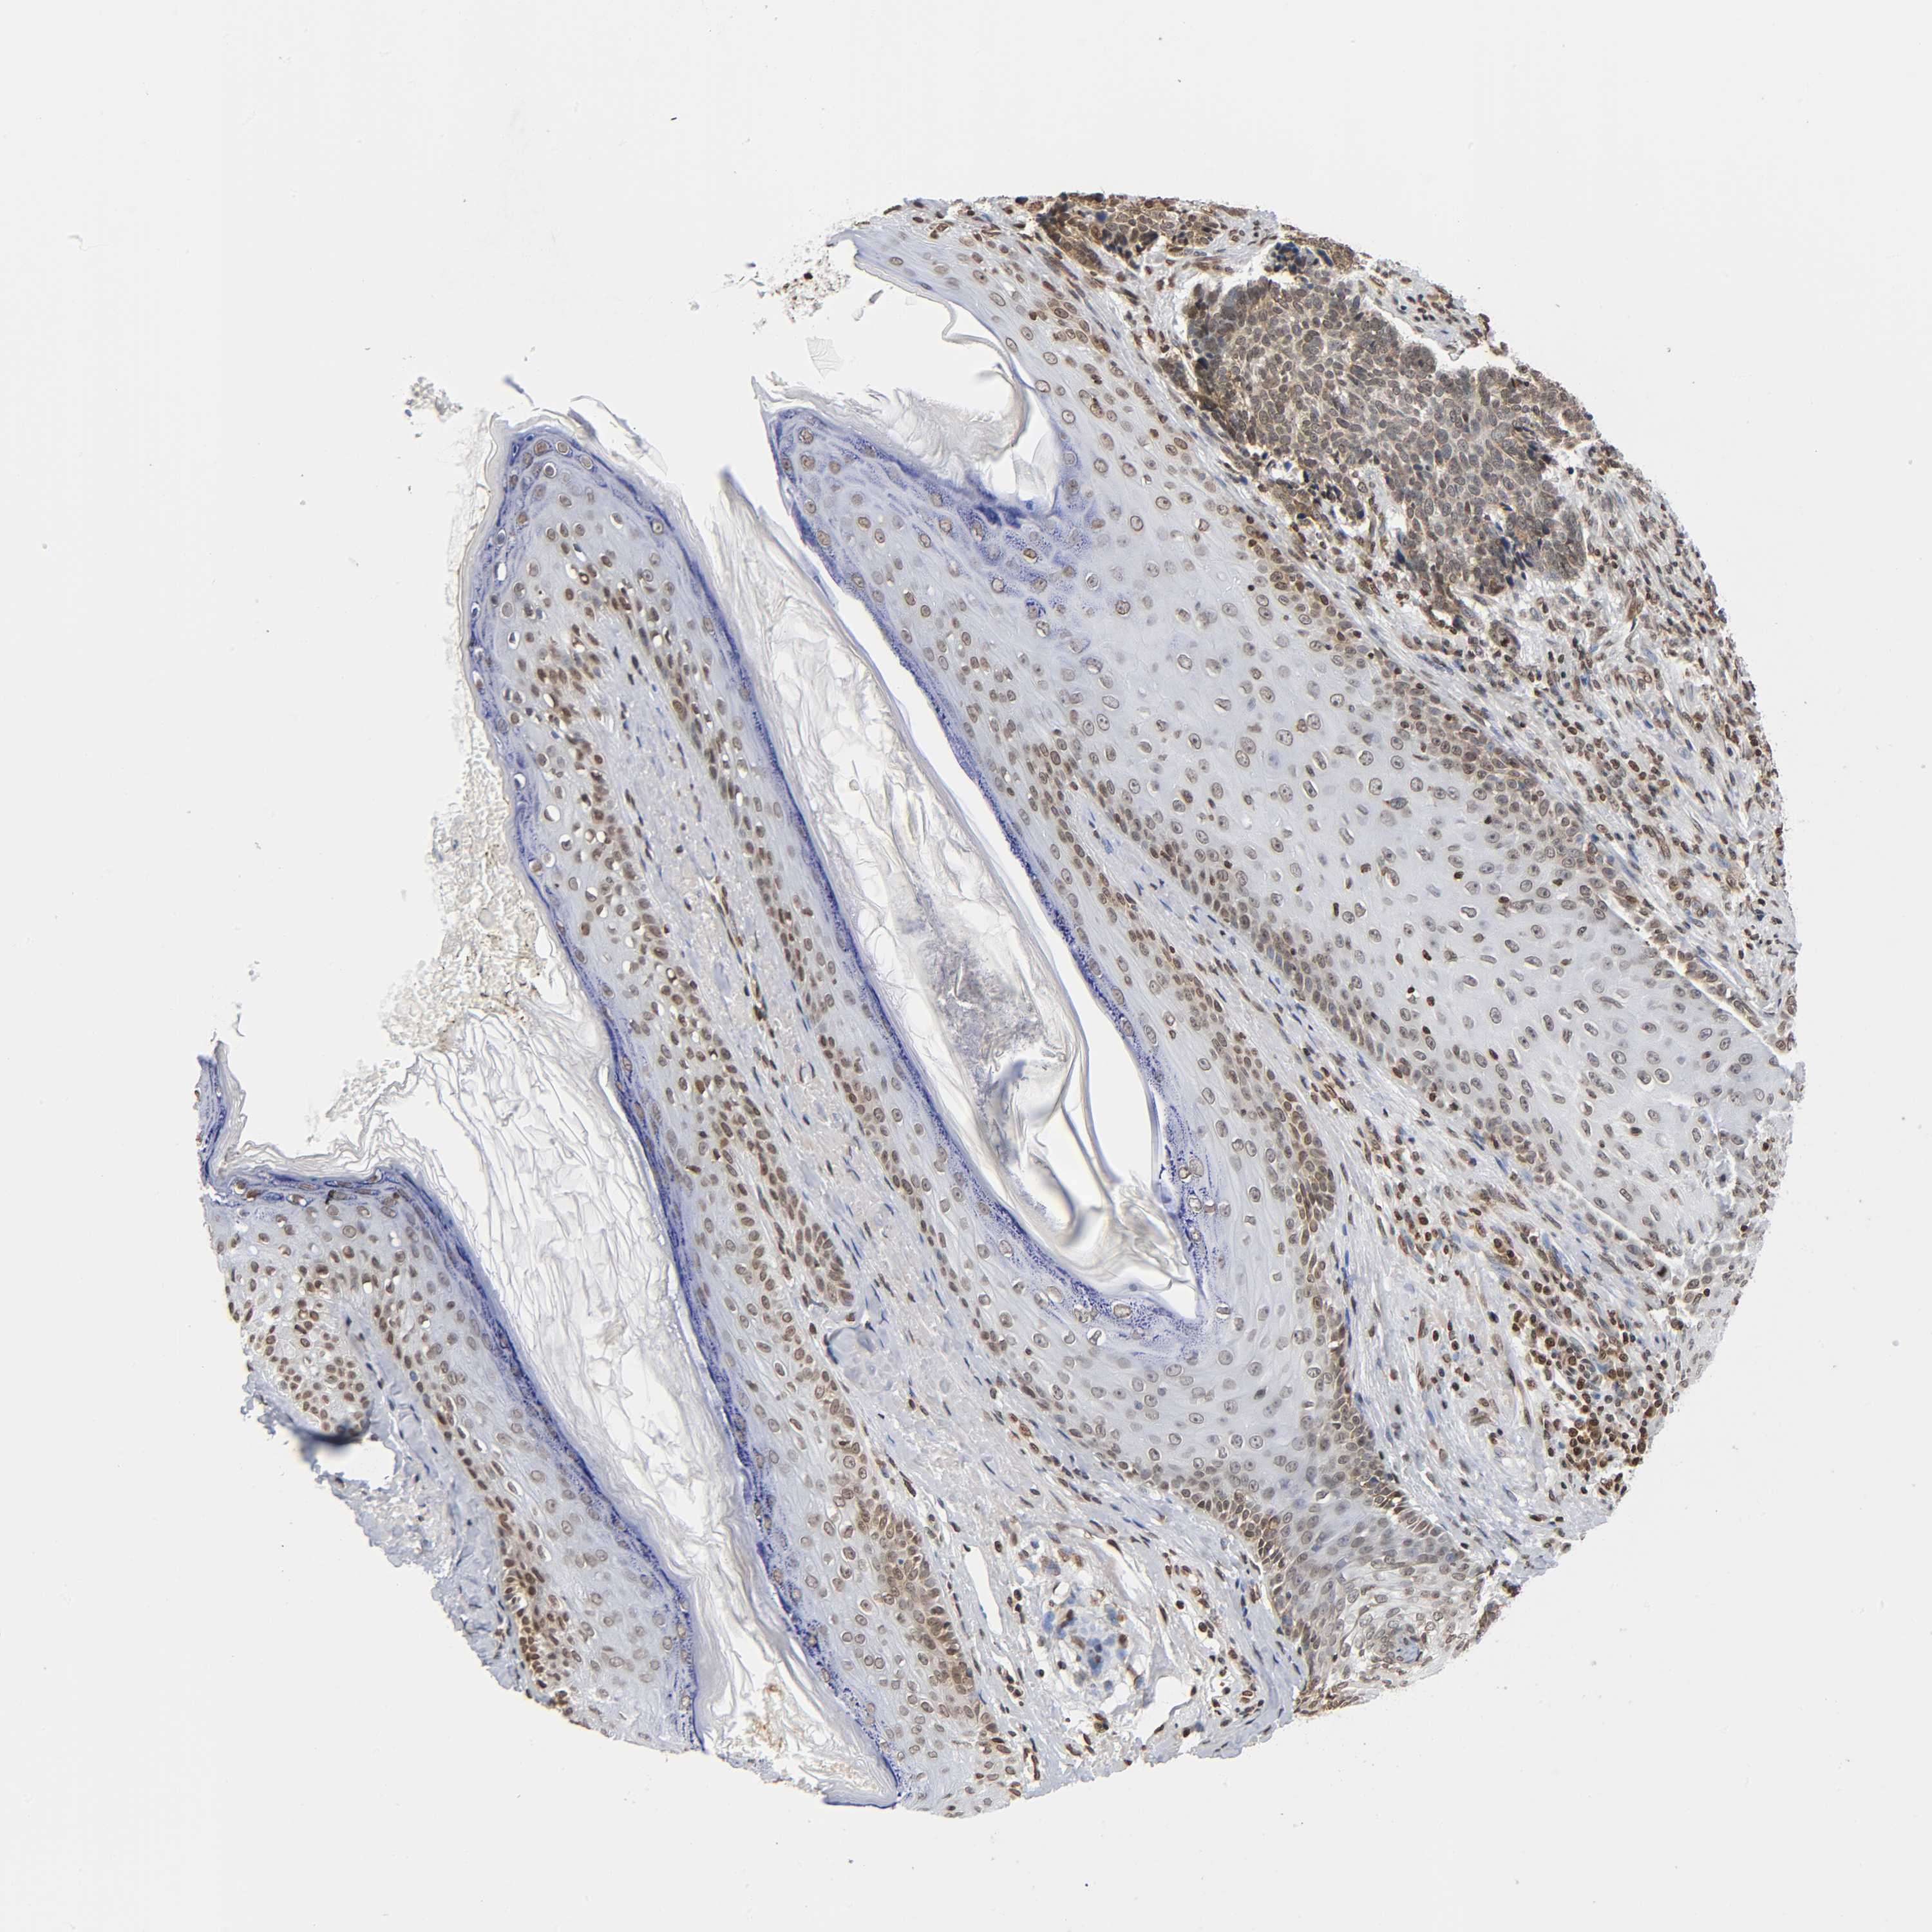

Basal cell and squamous cell cancer

SKIN CANCER - Protein expressioni

A mouse-over function shows sample information and annotation data. Click on an image to view it in a full screen mode. Samples can be filtered based on level of antibody staining by selecting one or several of the following categories: high, medium, low and not detected. The assay and annotation is described here.

Antibody stainingi

Antibody staining in the annotated cell types in the current human tissue is reported as not detected, low, medium, or high, based on conventional immunohistochemistry profiling in selected tissues. This score is based on the combination of the staining intensity and fraction of stained cells.

Each image is clickable and will lead to virtual microscopy that enables deeper exploration of all samples and also displays staining intensity scores, fraction scores and subcellular localization as well as patient and tissue information for each sample.

Antibody HPA004203

Staining

High

Intensity

Strong

Quantity

>75%

Location

Nuclear

Squamous cell carcinoma, NOS